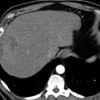

Sán lá gan

» Thông tin: Nam giới – 52 tuổi.

» Lâm sàng: Kiểm tra sức khỏe.